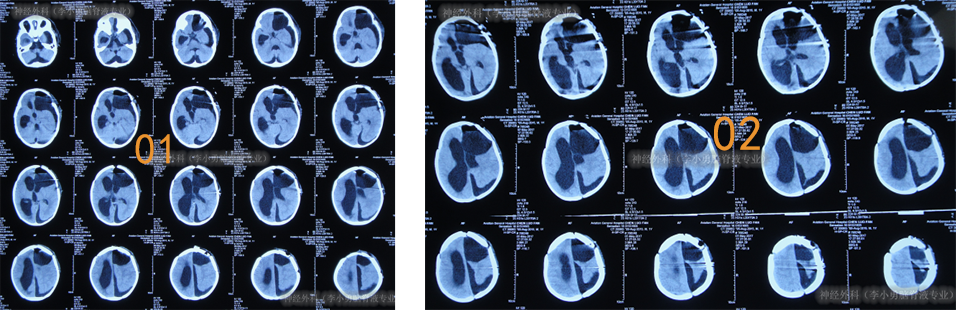

继续治疗1月的时间,期间患儿身体状态变得越来越好,情绪愉悦,肢体活动正常,期间2次查头颅CT均示脑室进一步缩小(图-21)。

图-21:2017年8月3日

2017年10月8日(李小勇脑脊液专业治80天)出院,出院时:精神状态好,肢体活动正常,能自己走路稍不稳,可简单言语交流;头围由入院时55cm缩小至51.5cm(图-22);出院时头颅CT示脑室分流术后状态,无异常(图-23)。

图-22:2017年10月8日

图-23:2017年10月8日头颅CT